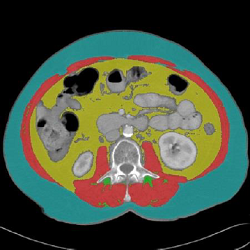

Tagged CT Scan

Tissue

TAG Name

TAG Color

Lower threshold limit

Upper threshold limit

Skeletal muscle

Muscle

1 - Red

-29

150

Intermuscular adipose tissue

IMAT

2 - Green

-190

-30

Visceral adipose tissue

VAT

5 - Yellow

-150

-50

Subcutaneous adipose tissue

SAT

7 - Cyan